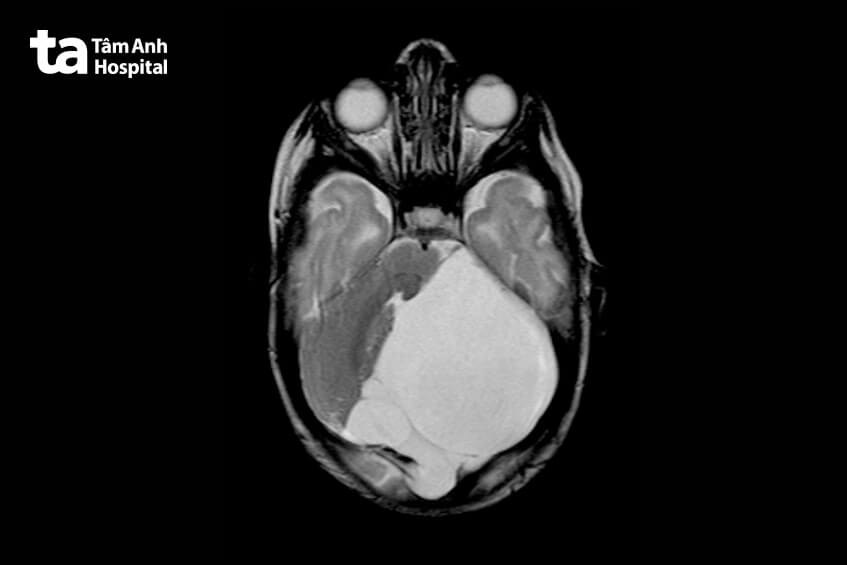

Nang màng nhện có thể xuất hiện ở bất kỳ khu vực nào trong não, nhưng phổ biến nhất ở hố sọ giữa (gần thùy thái dương), vùng góc cầu tiểu não, rãnh liên bán cầu và hố sọ sau. Những nang này có thể có kích thước nhỏ hoặc lớn, tùy thuộc vào từng trường hợp cụ thể. Nang màng nhện thường được phát hiện qua siêu âm thai nhi ở tam cá nguyệt thứ hai nhưng trong một số trường hợp, có thể cần MRI thai nhi để đánh giá chính xác hơn về kích thước và ảnh hưởng của nang. (1)

Chẩn đoán nang màng nhện ở thai nhi chủ yếu được thực hiện thông qua siêu âm thai. Siêu âm là phương pháp an toàn và hiệu quả nhất giúp phát hiện những bất thường trong não của thai nhi bao gồm cả u nang màng nhện. Thông qua siêu âm 3D hoặc 4D, bác sĩ có thể quan sát chi tiết các cấu trúc trong não và phát hiện những bất thường ngay từ giai đoạn giữa thai kỳ.

Bên cạnh phương pháp siêu âm, trong một số trường hợp cần thiết, bác sĩ có thể chỉ định thai phụ thực hiện một số các kỹ thuật chẩn đoán hình ảnh và các xét nghiệm bổ sung khác như MRI thai, NIPT, chọc ối,… để kiểm tra các bất thường nhiễm sắc thể và các yếu tố di truyền khác. Những phương pháp này hỗ trợ bác sĩ xác định được nguyên nhân gây ra nang màng nhện và đánh giá được chính xác mức độ nguy hiểm của tình trạng này.